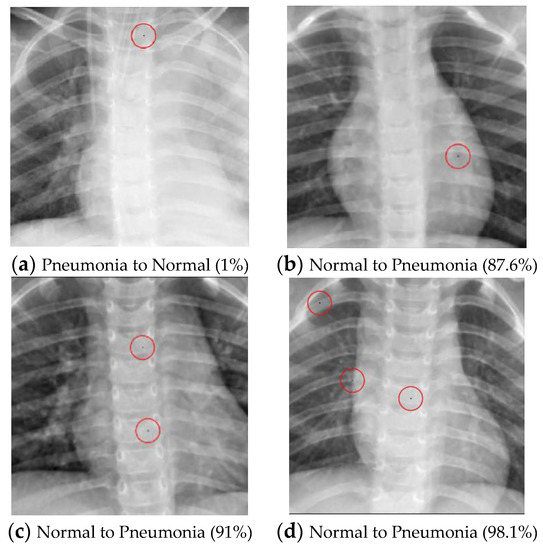

Pneumonia (Multi-pixel)

The Pneumonia dataset encompasses two different image classes, namely “Normal” and “Pneumonia”. A multi-pixel attack strategy was used on both classes in this research with the objective of transforming the images into their respective opposite categories.

As illustrated in Table 10, the success rate of converting normal images into pneumonia images is positively correlated with the number of perturbed pixels. However, the algorithm’s performance in transforming pneumonia images into normal images does not yield successful results, even with an increase in the perturbed pixels. The successful attack images are shown in Figure 4.

Figure 4. Examples of the attack results on the Pneumonia dataset with confidence level of ResNet50: (a) One-pixel attack turning Pneumonia to Normal; (b) One-pixel attack turning Normal to Pneumonia; (c) Two-pixel attack turning Normal to Pneumonia; (d) Three-pixel attack turning Normal to Pneumonia.